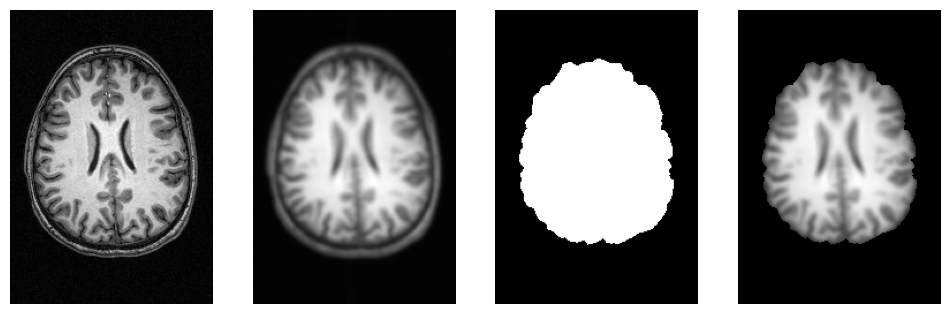

# Helper function to plot 3D NIfTI images

f = plt.figure(figsize=(12, 4))

for i, img in enumerate([input_file,

opj(wf_work_dir, "smoothflow/smooth/sub-01_T1w_smooth.nii.gz"),

opj(wf_work_dir, "smoothflow/skullstrip/sub-01_T1w_brain_mask.nii.gz"),

opj(wf_work_dir, "smoothflow/mask/sub-01_T1w_smooth_masked.nii.gz")]):

f.add_subplot(1, 4, i + 1)

plot_slice(img)